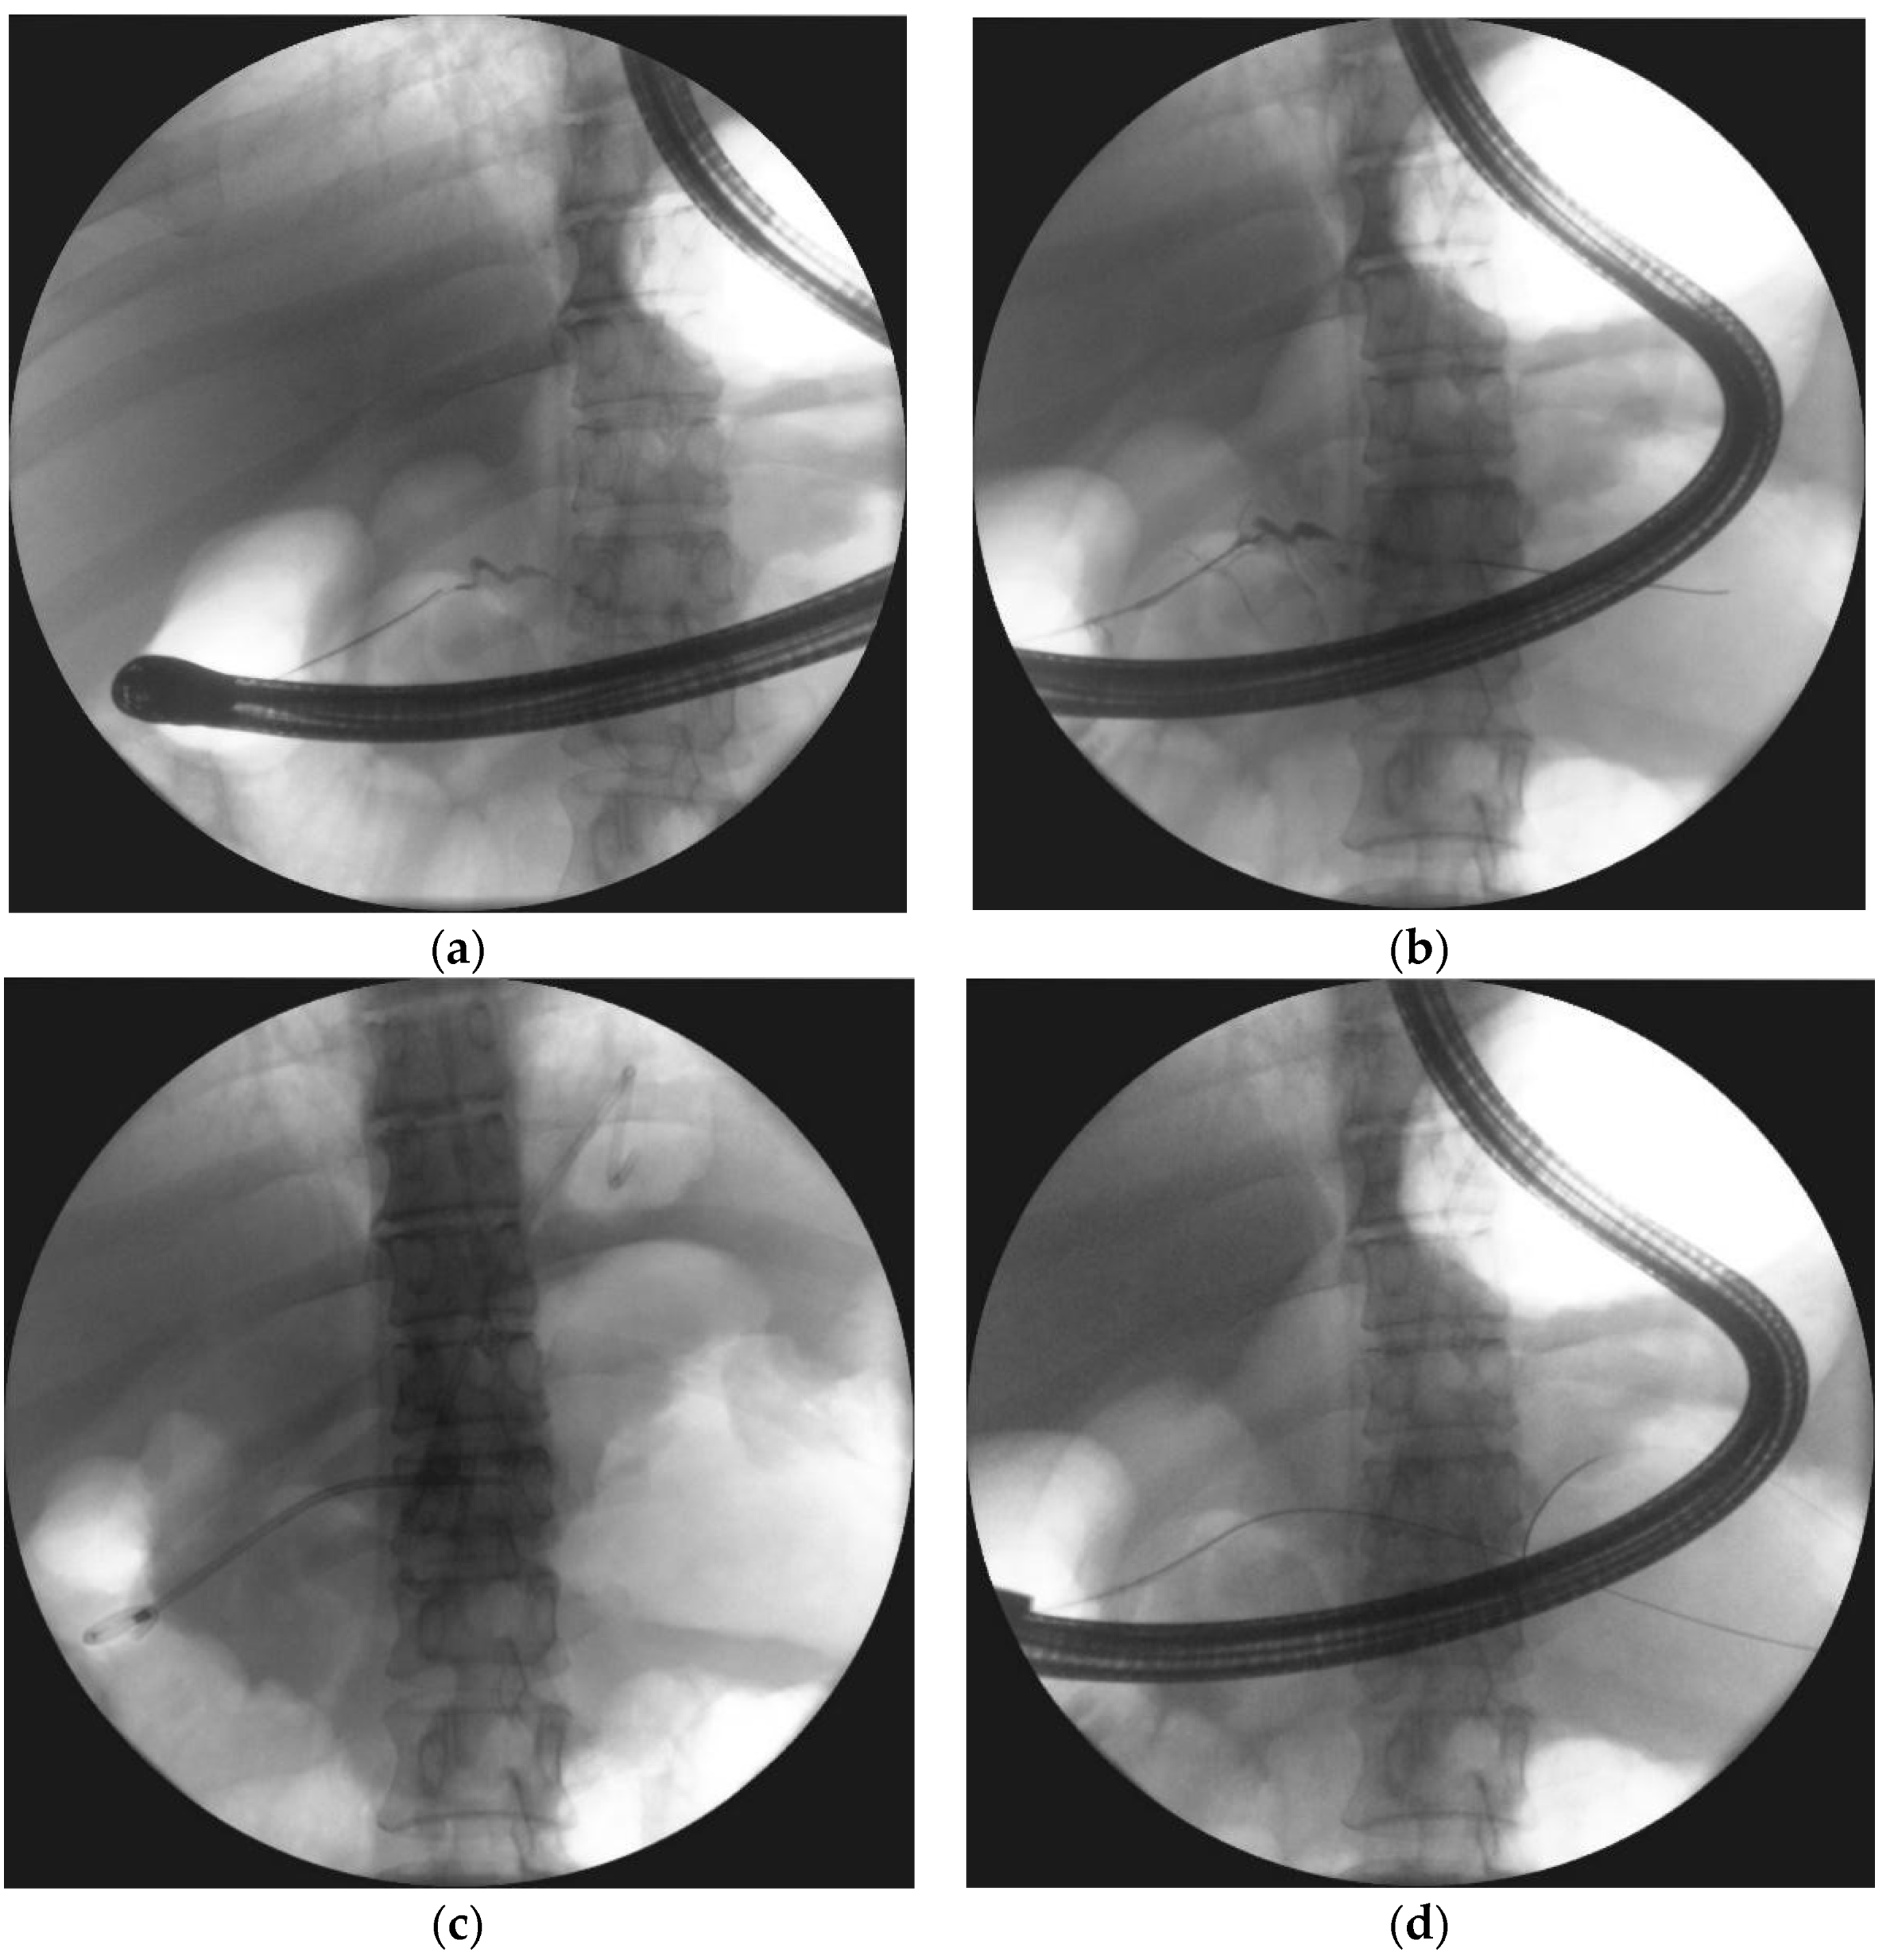

- Smoczyński, M.; Jagielski, M.; Siepsiak, M.; Adrych, K. Endoscopic necrosectomy through the major duodenal papilla under fluoroscopy imaging. Arch. Med. Sci. 2018, 14, 470–474. [Google Scholar] [CrossRef] [PubMed]

| Passive transpapillary drainage | The insertion endoscopic pancreatic stent to pancreatic duct through duodenal papilla. |

| Active transpapillary drainage | Endoscopic insertion pancreatic endoprosthesis as well as nasal drain to pancreatic duct through duodenal papilla. |